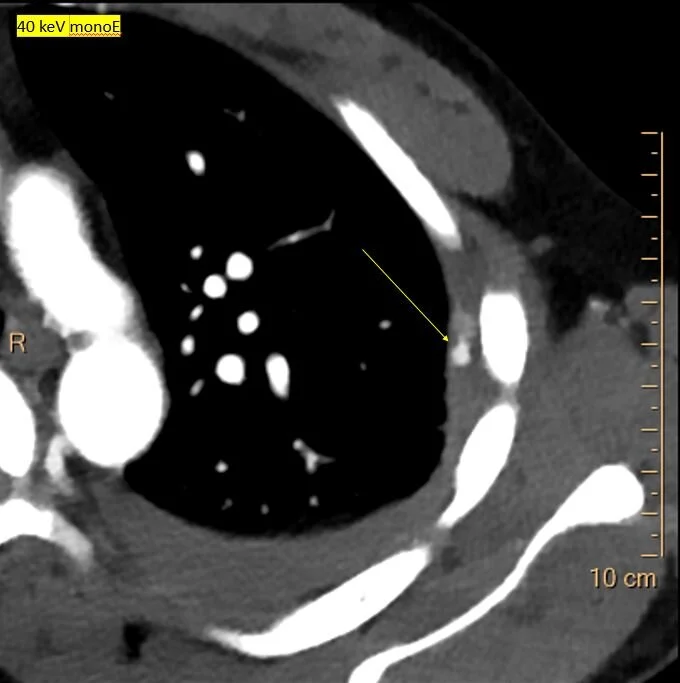

40 keV monoE: Nicely depicts the aneurysm!